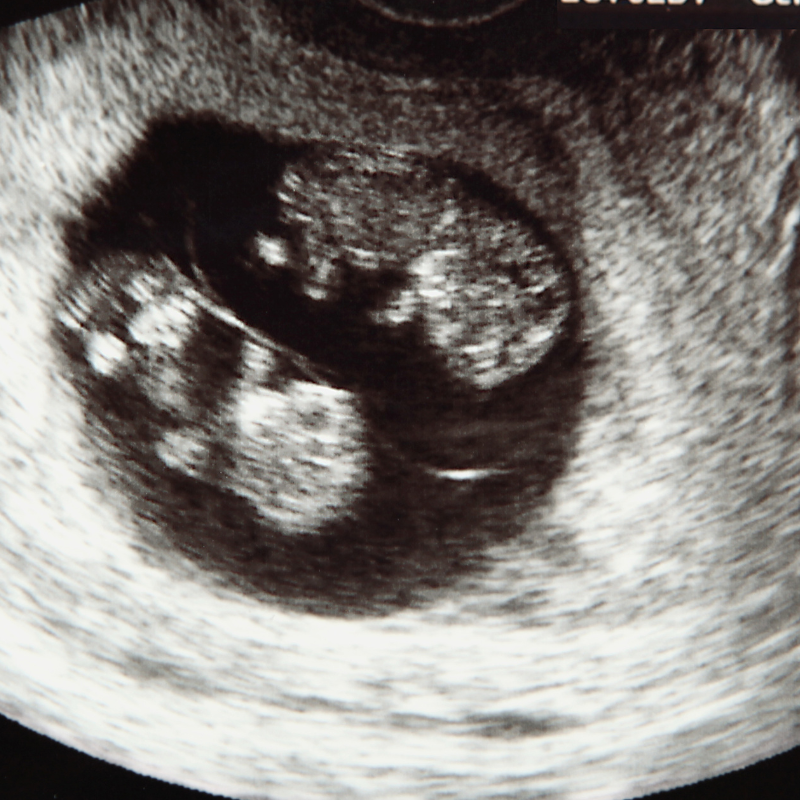

Reading Time: 3 minutesSharp corners. Exposed outlets. Dishpods…oh my! If you just saw two heartbeats on an ultrasound, chances are…these…